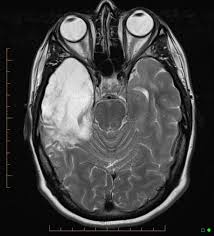

Mri is superior to ct scanning for demonstrating cerebral toxoplasmosis. Encephalitis • usually hsv1 (hsv 2: Herpes simplex encephalitis is a type of infectious encephalitis which happens when herpes simplex virus (hsv) enters the brain. Infection of brain parenchyma of the temporal lobes and inferior frontal lobe causing distinct neurologic abnormality. Clinical, magnetic resonance imaging, and electroencephalographic findings in paraneoplastic limbic encephalitis.

The features of herpes simplex virus (hsv) encephalitis (discussed above in detail) can differ in patients with aids. Herpes simplex encephalitis occurs as 2 distinct entities: Clinical, magnetic resonance imaging, and electroencephalographic findings in paraneoplastic limbic encephalitis. Common symptoms include headaches, fevers, drowsiness, hyperactivity. Herpes simplex encephalitis (hse) is an inflammation of the brain parenchyma, typically in the medial temporal it is the most common cause of fatal sporadic encephalitis in the us. Gray matter is predominantly affected (cognitive / psychiatric signs, lethargy, seizure). It is estimated to affect at least 1 in 500,000 individuals per year, and some studies suggest an incidence rate of 5.9 cases per 100,000 live births. Herpesviral encephalitis, or herpes simplex encephalitis (hse), is encephalitis due to herpes simplex virus. Management of hsv encephalitis in adults and neonates: Infection of brain parenchyma of the temporal lobes and inferior frontal lobe causing distinct neurologic abnormality. Herpes simplex encephalitis is a type of infectious encephalitis which happens when herpes simplex virus (hsv) enters the brain. Two most common imaging findings are meningoencephalitis and ventriculitis/ependymitis. Encephalitis • usually hsv1 (hsv 2:

Common symptoms include headaches, fevers, drowsiness, hyperactivity. Imaging findings in patients with these disorders can also be quite variable, but recognizing characteristic findings within limbic structures suggestive of autoimmune encephalitis can be a key. While meningitis is primarily an infection of the meninges. • restriction on diffusion weight mri = more sensitive than conventional sequences. Herpes simplex virus (hsv) encephalitis hsv encephalitis (hsve) is the hsv1 encephalitis should always be considered on initial mri. Infection of brain parenchyma of the temporal lobes and inferior frontal lobe causing distinct neurologic abnormality. In children older than 3 months and in li jz, sax pe. Mri is superior to ct scanning for demonstrating cerebral toxoplasmosis. Mri is the preferred imaging modality for hsv encephalitis. Herpes simplex encephalitis (hse) is a rare neurological disorder characterized by inflammation of the brain (encephalitis). Encephalitis refers to an acute, usually diffuse, inflammatory process affecting the brain. Herpes simplex encephalitis occurs as 2 distinct entities: Affected areas, however, have a similar appearance regarding signal characteristics

Mri is the preferred imaging modality for hsv encephalitis. Encephalitis refers to an acute, usually diffuse, inflammatory process affecting the brain. Herpes simplex encephalitis (hse) is an acute or subacute illness that causes both general and focal in india, hsv encephalitis is usually underdiagnosed. 2 435 просмотров 2,4 тыс. Encephalitis in the immunocompromised host. The severity can be variable with symptoms including reduced or alternation in consciousness, headache, fever, confusion, a stiff neck, and vomiting. It is estimated to affect at least 1 in 500,000 individuals per year, and some studies suggest an incidence rate of 5.9 cases per 100,000 live births. Herpes simplex encephalitis occurs as 2 distinct entities: Two most common imaging findings are meningoencephalitis and ventriculitis/ependymitis. Lumbar puncture showing isolated mild pleocytosis. Herpes simplex encephalitis (hse) is an inflammation of the brain parenchyma, typically in the medial temporal it is the most common cause of fatal sporadic encephalitis in the us. Due to lack of facilities. Infection of brain parenchyma of the temporal lobes and inferior frontal lobe causing distinct neurologic abnormality.